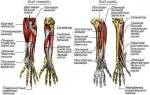

Чтобы понять причину появления боли в ногах, нужно вспомнить, что нижняя конечность состоит из бедра, голени и ступни. Часть людей точно указывают месторасположение боли, а некоторые даже не могут понять, где она локализована. В этом случае они говорят, что в ноге «крутит», «ноет», «тянет».

Болевые ощущения в ступнях, голенях и бедрах, которые беспокоят после использования тесных туфель или выраженной нагрузки, снимаются при помощи массажа. Перед ним лучше всего принять ванну для расслабления мышц.

Разминание и растирание позволят снять спазмы и улучшить отток крови. Поначалу рекомендуется обратиться к специалисту, который проведет процедуру правильно или покажет необходимые движения, но можно сделать массаж и самостоятельно.

Движения руками должны быть плавными и без сильного нажатия. Сидя на твердой ровной поверхности, нужно идти по направлению снизу вверх. Сначала обрабатывается область голеностопа, а затем голень и колено. После этого следует разминать ступню.